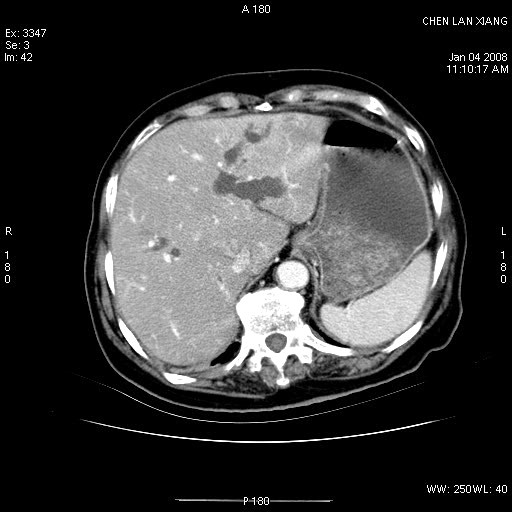

标题: CT11180:女,76岁,腹痛3-4天 [打印本页]

标题: CT11180:女,76岁,腹痛3-4天

女,76岁,腹痛3-4天,b超示:肝内实性肿物,胆囊强回声,胆总管扩张.

考虑:1、胆总管下端结石伴梗阻性肝内外胆管扩张(肝左叶外侧段肝内胆管多发结石、胆管炎);

2、肿囊癌累及肝,不除外 黄色肉芽肿性胆囊炎。

1 胆总管末端结石伴肝内胆管结石,肝内外胆管扩张。2 胆囊扩大,胆囊壁不规则增厚,内见软组织密度影。考虑:慢性胆囊炎,不除外胆囊癌!

胆囊密度增高,增强后周边肝组织及胆囊窝下部周边软组织延时性不规则强化.然胆囊壁未见明显不规则增厚及肿块.左侧肝内胆管及胆总管下段结石伴胆系扩张.

考虑;胆囊炎(黄色肉芽肿性胆囊炎?),左侧肝内胆管及胆总管下段结石.

标题: 肝右叶病灶

胆囊癌侵犯肝右叶?

1)胆囊癌伴肝脏转移。2)胆总管下端结石、肝内胆管结石伴肝内外胆管扩张。